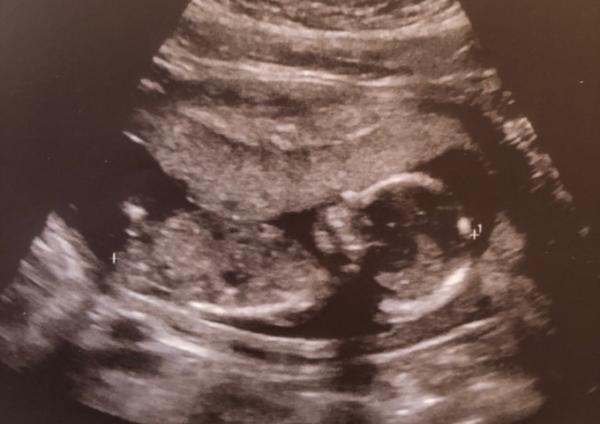

Mir kommt’s auch wie immer eine gefühlte Ewigkeit vor... momentan kann ich mich aber ganz gut beschäftigen indem ich ein wenig umräume und so... Wenn ich dann beim Termin war, denk ich allerdings so... wow... schon so groß das Baby... da gehts dann irgendwie doch recht schnell... Anbei auch ein aktuelles Bild von gestern (15+3) Liebe Grüße Yvonne

Bild zu